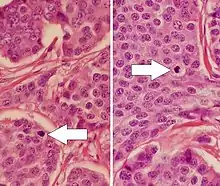

NETs are often small, yellow or tan masses, often located in the submucosa or more deeply intramurally, and they can be very firm due to an accompanying intense desmoplastic reaction. The overlying mucosa may be either intact or ulcerated. Some GEP-NETs invade deeply to involve the mesentery.[72] Histologically, NETs are an example of "small blue cell tumors," showing uniform cells which have a round to oval stippled nucleus and scant, pink granular cytoplasm. The cells may align variously in islands, glands or sheets. High power examination shows bland cytopathology. Electron microscopy can identify secretory granules. There is usually minimal pleomorphism but less commonly there can be anaplasia, mitotic activity, and necrosis.